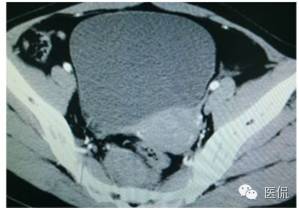

女,37岁,体检超声发现盆腔包块一周。无其他异常。

增强动脉期(CT值31HU)